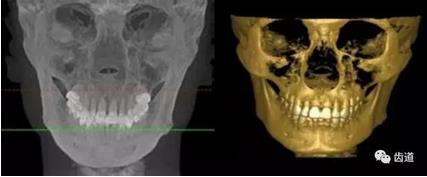

五)口腔正畸

CBCT在頜骨正畸科方面的應(yīng)用:軟件功能的強大,提供有效的數(shù)據(jù),為頜骨正畸提供了極大的幫助,免除了很多臨床醫(yī)生的手工繪圖,并有利于科研、教學(xué)等方面發(fā)展研究。

投影測量側(cè)位片影像

軟件產(chǎn)生CEPH圖像注釋,不含X線射線圖像